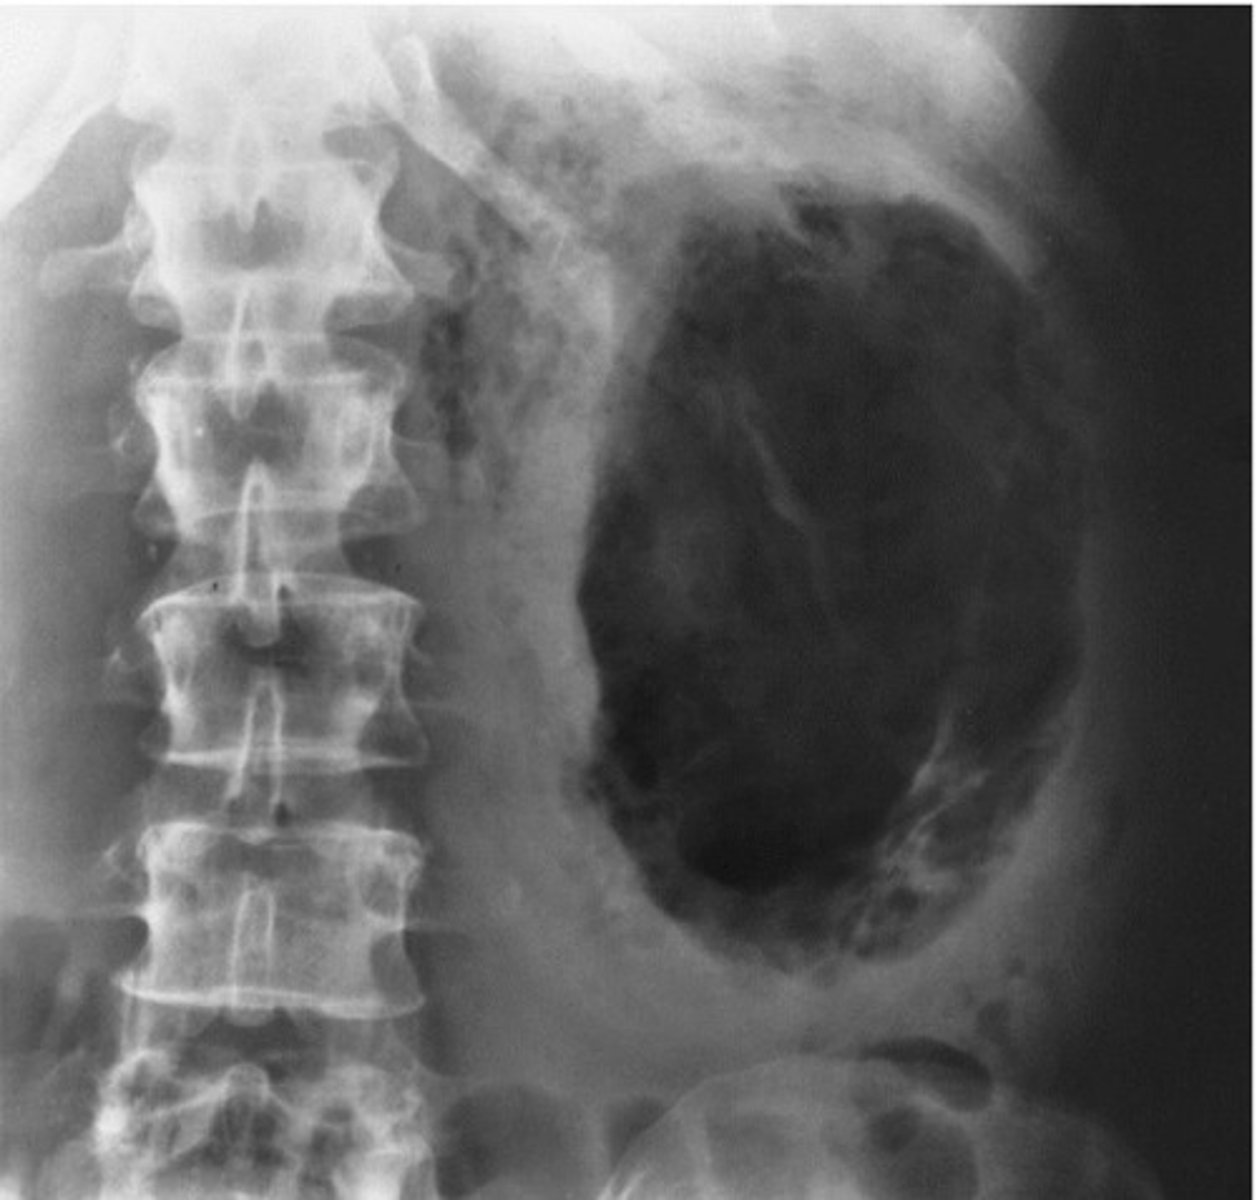

- Horseshoe Kidney

- Kidney stones

- What congenital anomaly occurs when the lower poles of the kidney fail to separate in the fetus and results in a horseshoe-shaped kidney?

- What can patients frequently develop because the ureters are displaced with this pathology?